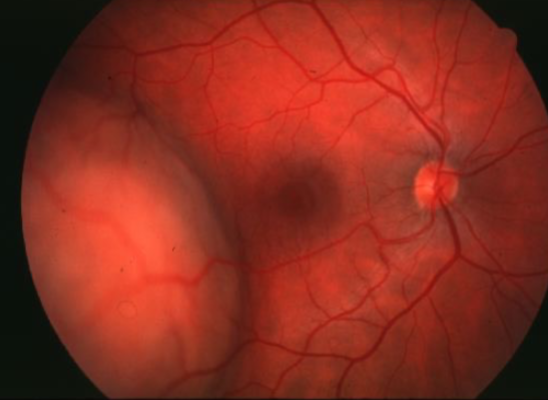

retinoblastoma

retinoblastoma

retinoblastoma

retinoblastoma

ocular manifestations:

leukocoria

strabismus

dome-shaped lesion

whitish pink nodular mass

can cause RRD

secondary glaucoma & pseudouveitis

endophytic

retinoblastoma type

white, pearly-pink, creamy nodular mass that breaks through the ILM into vitreous

vitreous seeding

fine blood vessels on surface

secondary calcification leads to sharp demarcations (cottage cheese)

exophytic

retinoblastoma type

yellowish subretinal mass lesion often underlying a serous RD

total RD risk

tumor is difficult to view